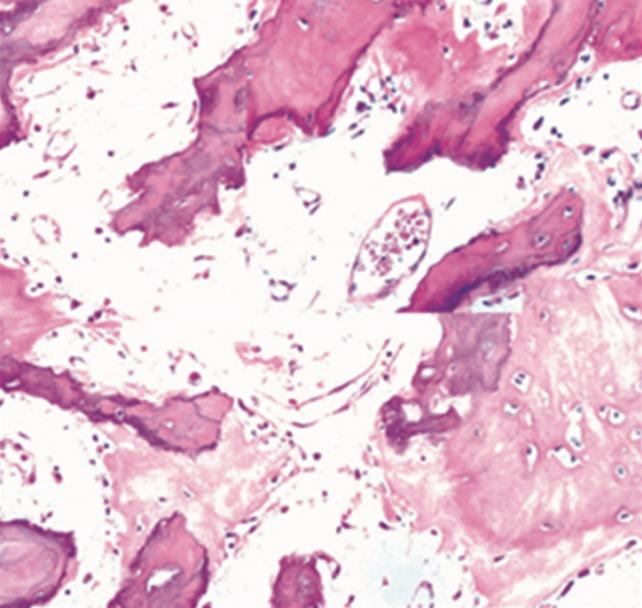

Paget disease is a metabolic disorder involving abnormal bone turnover that consists of 3 phases: the initial lytic phase, the intermediate mixed phase, and the chronic sclerotic phase. Paget disease mostly presents as polyostotic or monostotic lesions of the spine, and is rare on the Indian subcontinent. We present a case of isolated Paget disease of the lumbar third vertebra, which was confirmed only at biopsy. The patient presented with chronic low backache with a developing neurological deficit. We managed the patient with posterior spinal stabilisation, using pedicular screws and vertebroplasty of the collapsed vertebrae to regain the height. Upon the diagnosis of Paget disease, the patient was treated with calcitonin and bisphosphonates for 3 months, along with regular monitoring of alkaline phosphatase levels. Through this case, we hope to emphasize that Paget disease should be considered in the differential diagnosis of lytic lesions. Additionally, the alkaline phosphatase level in this patient was high-normal, which was an aspect of the role of Paget disease as a mimicker. Confirmatory biopsy is mandatory in all lesions.

佩吉特病是一种涉及异常骨转换的代谢性疾病,包括三个阶段:初始溶骨期、中间混合期和慢性硬化期。佩吉特病大多表现为脊柱的多骨或单骨病变,在印度次大陆较为罕见。我们报告一例仅在活检时确诊的第三腰椎孤立性佩吉特病病例。该患者表现为慢性下背痛并伴有逐渐发展的神经功能缺损。我们采用椎弓根螺钉进行后路脊柱稳定术,并对塌陷椎体进行椎体成形术以恢复高度,从而对该患者进行治疗。在诊断为佩吉特病后,该患者接受了3个月的降钙素和双膦酸盐治疗,并定期监测碱性磷酸酶水平。通过这个病例,我们希望强调在溶骨性病变的鉴别诊断中应考虑佩吉特病。此外,该患者的碱性磷酸酶水平略高于正常,这是佩吉特病作为一种模仿者的作用的一个方面。对于所有病变,确诊性活检是必不可少的。